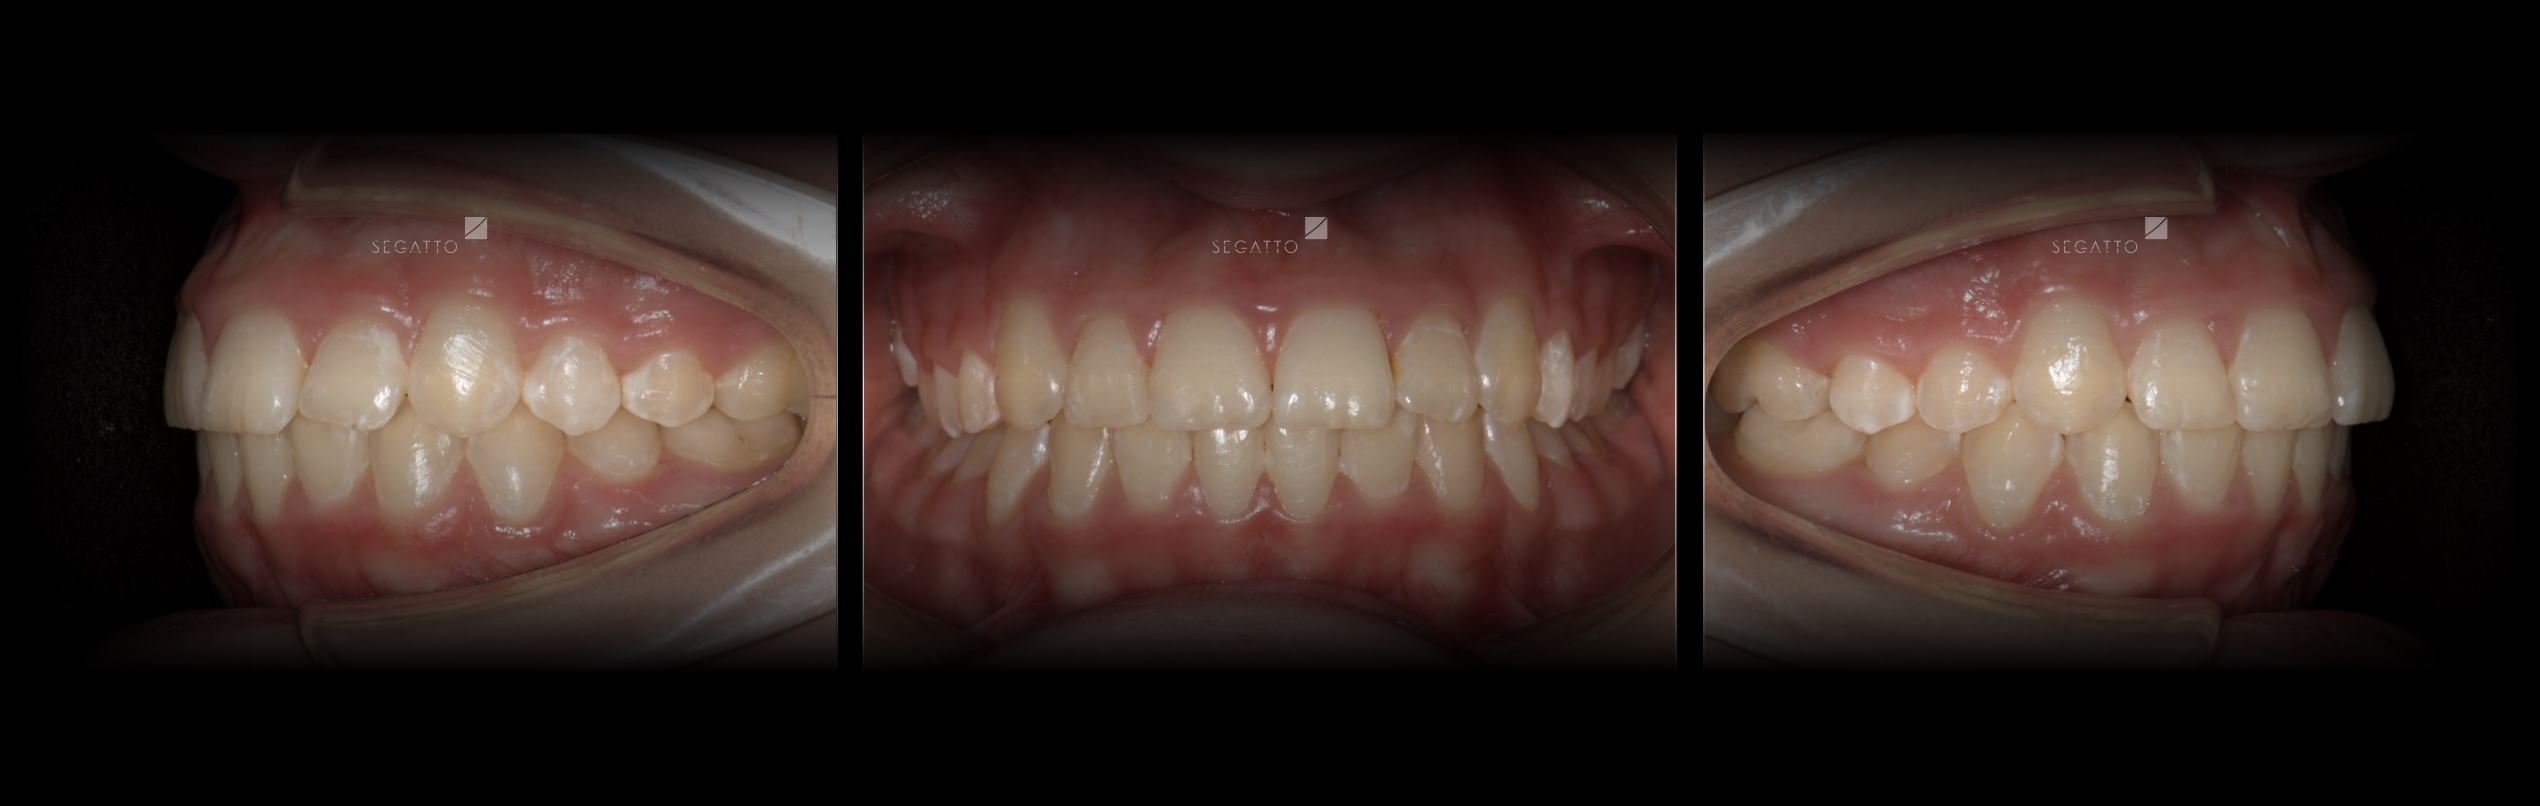

Orthodontics

Cases